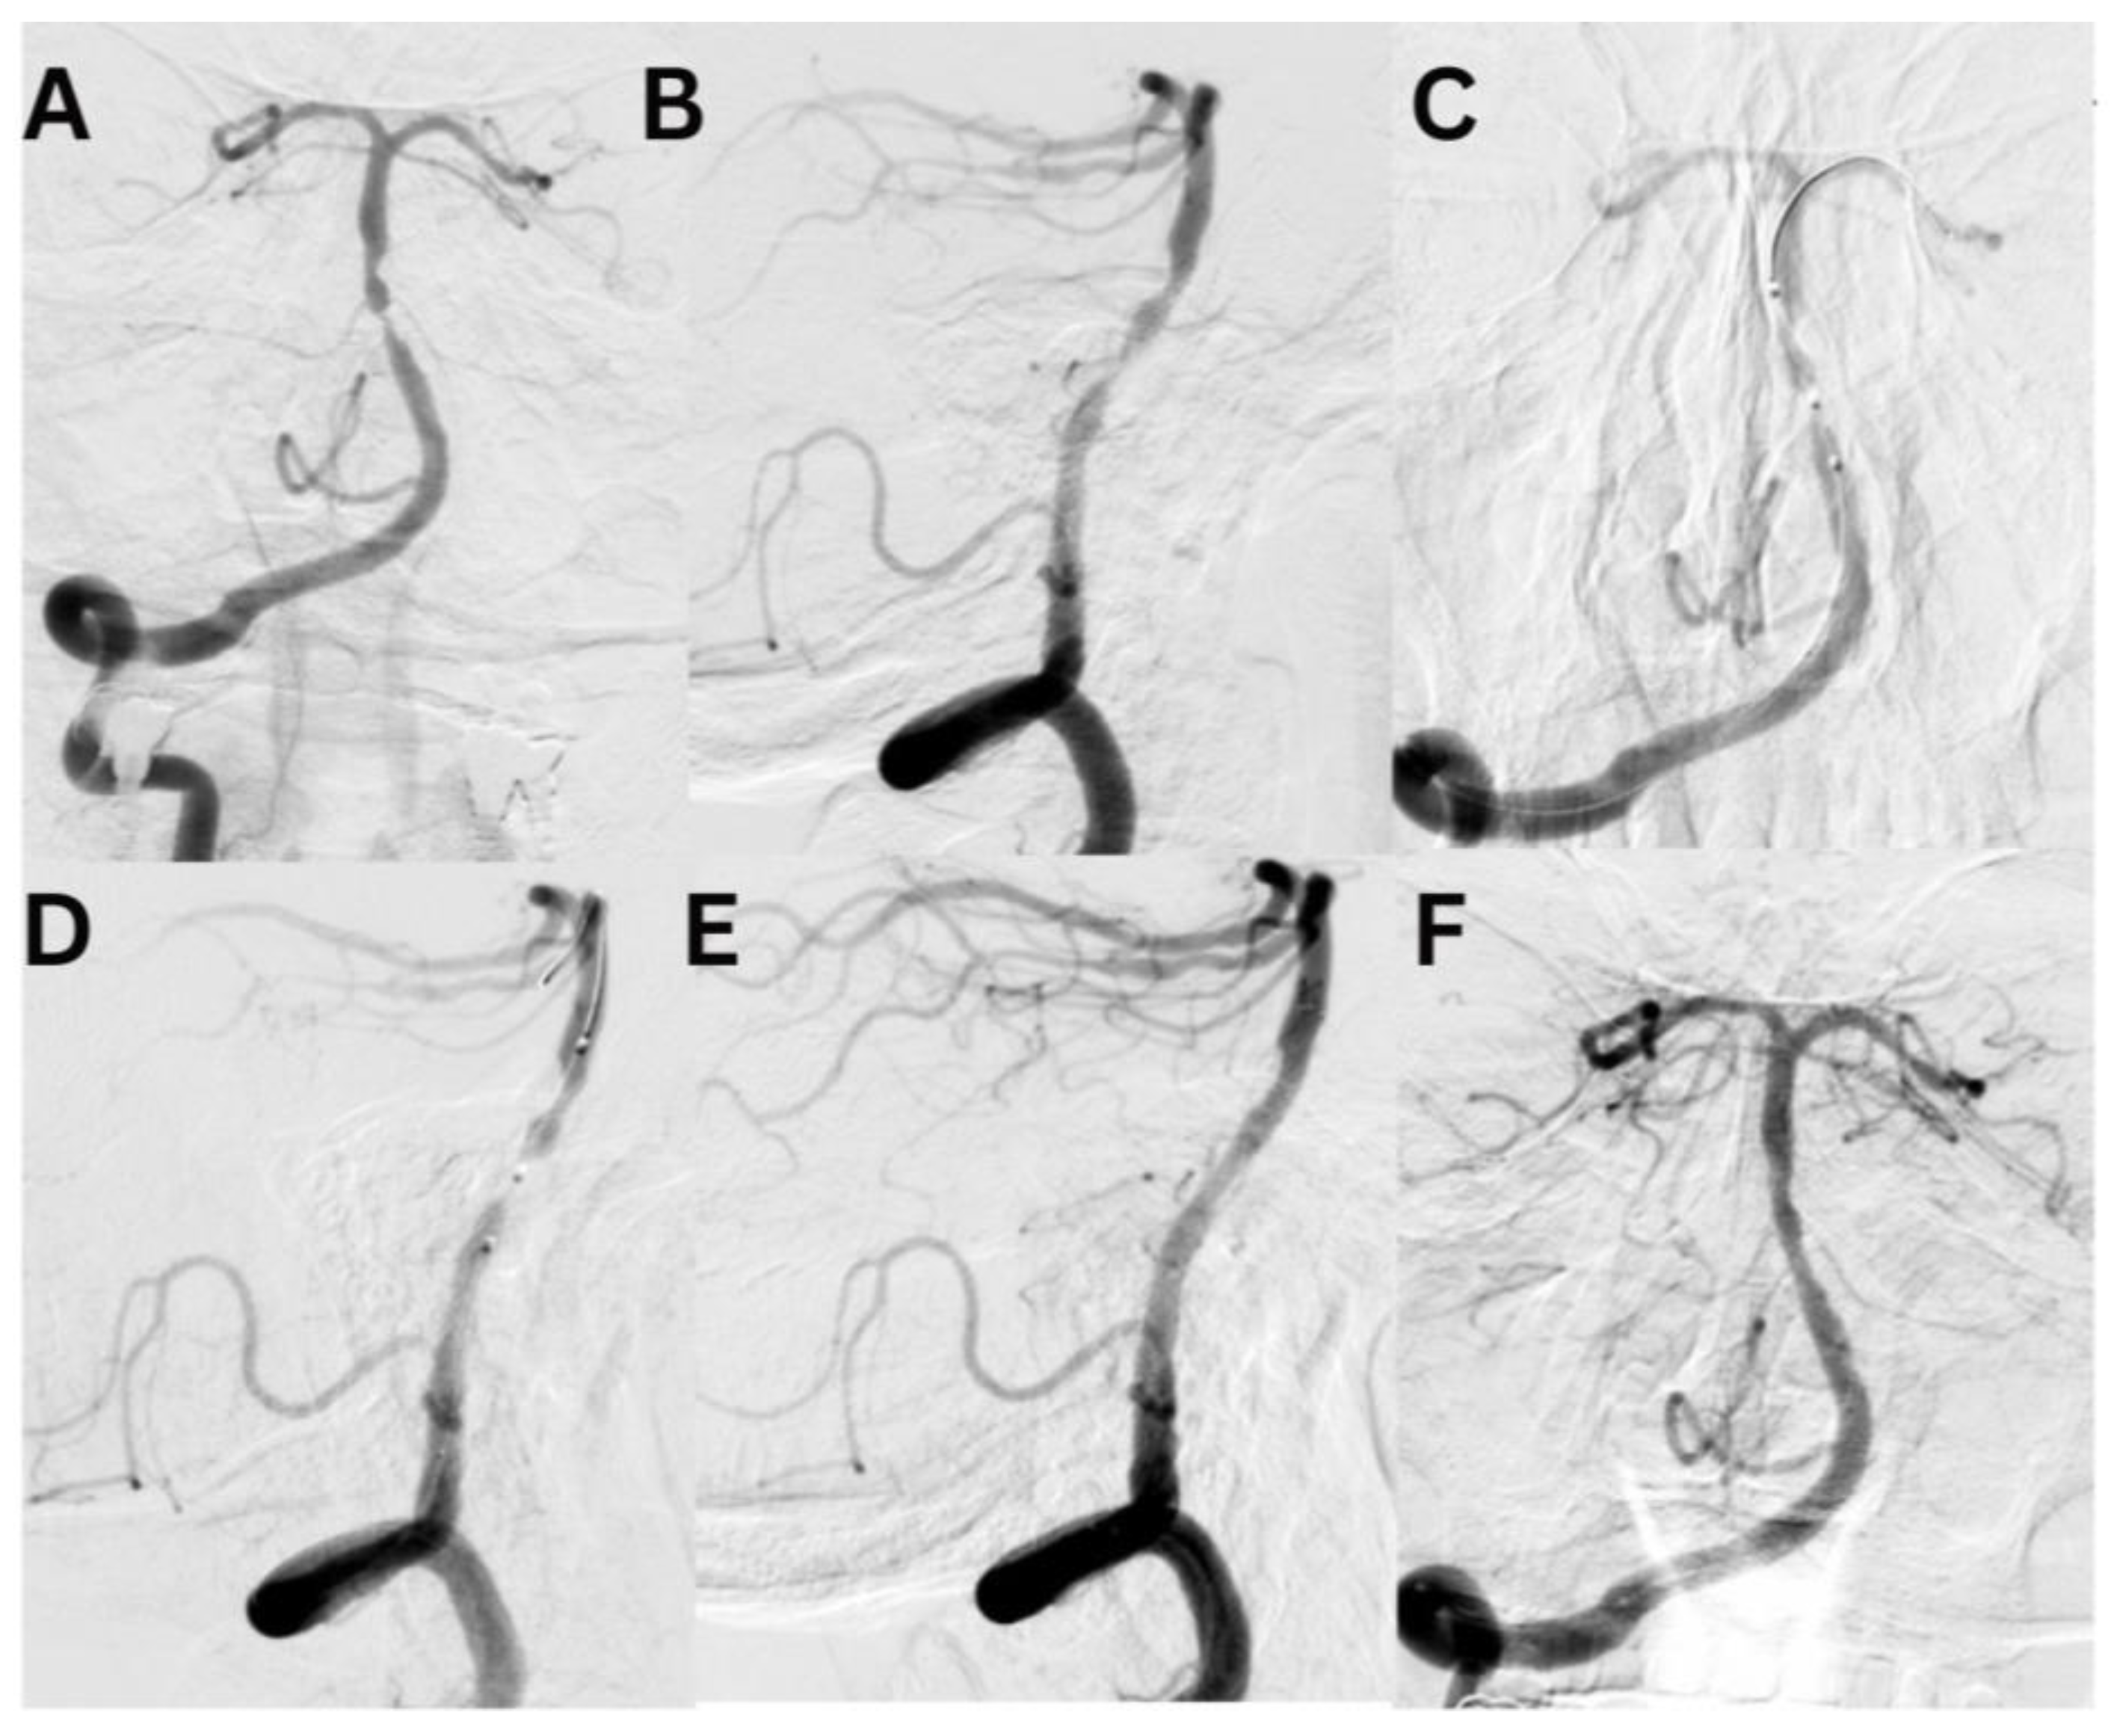

Case #1. A 75-year-old male patient with a history of myocardial infarction, type 2 diabetes mellitus, and hypertension presented with symptoms including slurred speech, temporary followed by full recovery, dizziness, tinnitus, unsteady gait, and lower extremity weakness. According to his wife, these symptoms began one week prior. Further diagnostic imaging with CTA revealed a subocclusion of the basilar artery, moderate stenosis in the V1 segment of the right vertebral artery, and hypoplasia of the left vertebral artery. Neurological examination at the time of admission was unremarkable. The patient was placed on dual antiplatelet therapy, and the VerifyNow test was performed, which detected no resistance. A surgical procedure was performed under local anesthesia. A 7Fr Fubuki guide catheter was inserted into the right vertebral artery, seen in Figure 3. Under surgical guidance, an ASAHI Sion blue 0.014x180cm microwire was advanced through the stenotic area. A NeuroSpeed 2x8mm catheter balloon was then advanced along the microcatheter, inflated twice for 2 seconds within the stenotic segment, resulting in a residual stenosis of up to 40%. Subsequently, a 5.0x25mm Credo intravascular stent was deployed through the NeuroSpeed catheter balloon. Angiographic control confirmed the elimination of the stenosis, and the arteries and veins were found to be patent. At the 3-month follow-up, the patient reported no complaints, and MRI did not show any new signs of stroke.

Figure 3. A diagnostic cerebral angiogram demonstrated an occlusion in the middle segment of the basilar artery on anteroposterior (A) and lateral (B) projections. Balloon angioplasty was performed, as shown in image C, followed by deployment of a Credo stent, as seen in image D. Subsequent control angiographies confirmed adequate stent placement and restoration of normal arterial flow on lateral (E) and anteroposterior (F) projections.